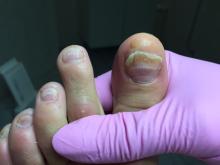

Bijgaand de nagels van een van mijn cliënten. Het gaat hier om een jonge vrouw, zij heeft maat 41 en redelijk lange tenen. Mevrouw heeft als kind met te kleine schoenen gelopen. De witte strepen overdwars lopen bij nagenoeg alle nagels op dezelfde hoogte: is hier sprake van een breuklijn, een beschadigd nagelbed, een mycose of beide? De witte strepen lijken geen oppervlakkige mycose want ik kreeg ze door middel van frezen niet weg. De nagels zijn dun en ik wilde niet verder frezen om splijten te voorkomen; de witte strepen zitten diep in de nagelplaat en lijken fijner van structuur dan de gele verkleuring. De gele verkleuring (waarvan mijn vermoeden een mycose is) liet zich wel goed verwijderen.

Hartelijk dank voor het meesturen van de foto’s. Het is altijd moeilijk om een juiste diagnose te stellen van een foto. Maar hier lijkt sprake van Leuconychia transversa. Deze aandoening die kan ontstaan als een reactie op een trauma (bv door te kleine schoenen), kenmerkt zich door witte, dwarslopende, banden over de nagelplaat. Er zijn ook andere reden voor het ontstaan van leuconychia transversa zoals bijvoorbeeld chemotherapie, infecties, (acute) stress. Leuconychia transversa kan ook erfelijk zijn.

De nagel van de hallux van de linkervoet betreft een stootnagel. Hier is mogelijk een trauma van de hallux aan voorafgegaan. Het is zinvol om samen met jouw cliënt na te gaan wat de mogelijk oorzaak is van het ontstaan van de leuconychia. Zijn de huidige schoenen adequaat? Draagt mevrouw adequate kousen/sokken? Sport mevrouw en zijn de sport en/of de sportschoenen mogelijk de oorzaak voor het ontstaan van de nagelbeschadigingen? Is mevrouw behandeld tegen kanker? Heeft mevrouw een neurologische aandoening, een vaataandoening of andere aandoening? Gebruikt mevrouw medicatie?

Of hier ook sprake is van een onychomycose, is op basis van de foto’s niet te zeggen. Hiervoor zal een biopt moeten worden afgenomen. Het vermoeden bestaat dat er eerder sprake is van overmatige mechanische stress op de nagelplaat waardoor deze problemen ontstaan.